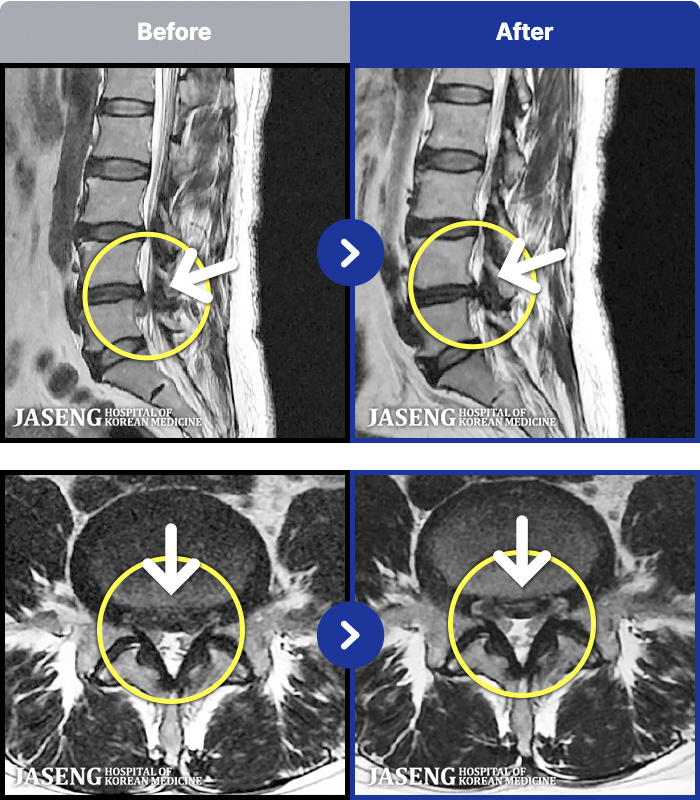

MRI ġ

88 MRI ũ ʸ Ȯϼ.